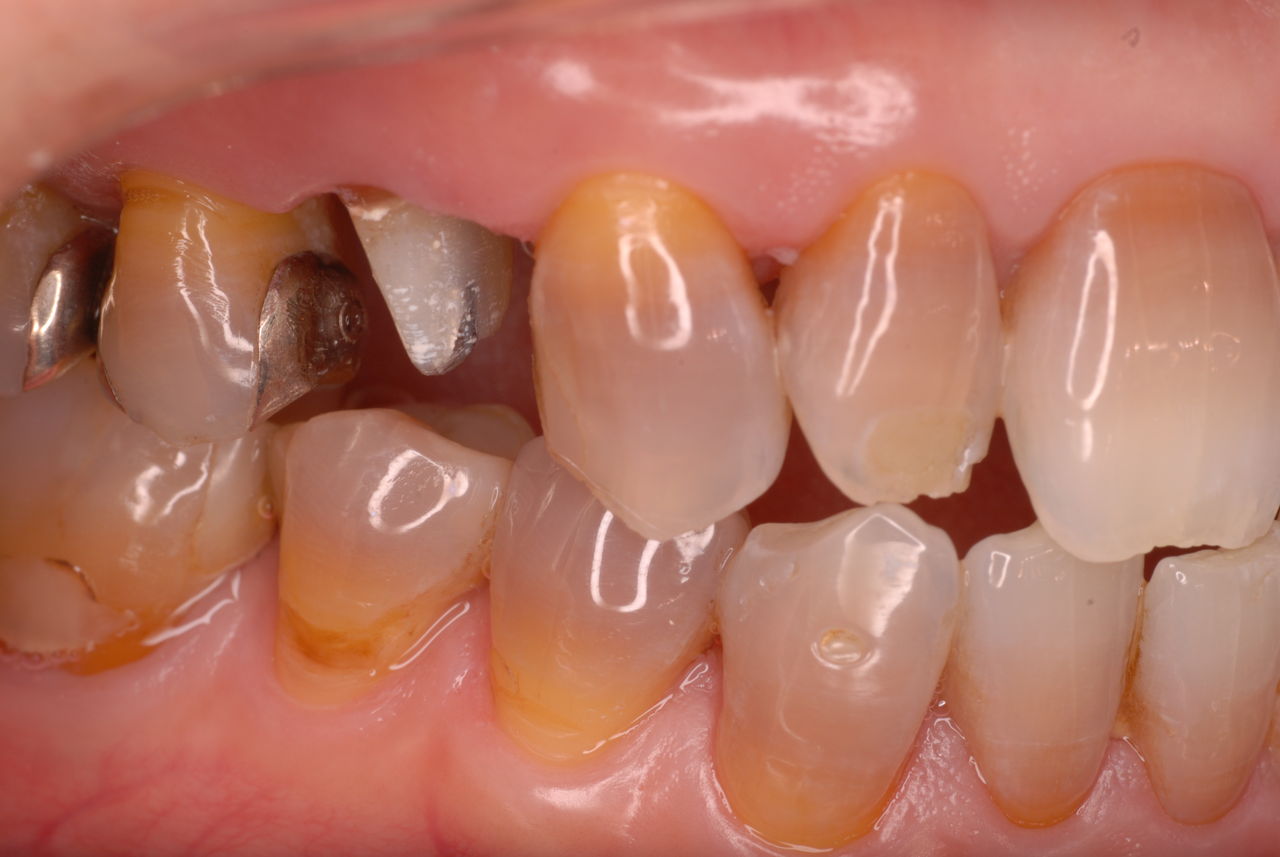

下顎、殆ど歯はなく歯周病で抜けそうな歯と虫歯だらけの歯、適合の悪い銀歯が入っていてそれも虫歯と歯周病で危ない状態でした。入れ歯は下の入れ歯は入れたことがないようです。(ため息)痛くて入れたことがないそうです。

左下の歯は歯の中の治療も?ですごい歯周病を患い歯茎の穴(ポケットと呼ばれるところ)から膿が出ているのです。ばい菌と毒素で骨が溶けて深い穴ができてそこにまたバイキンと毒素がたまるという悪循環ができているのですね。

右下の歯は歯の中の治療もあやしいのですが、金属と歯の間がすでに虫歯で崩壊し始めています。

プラークというバイキンと毒素と食べかすの塊が歯の周りや歯茎にまとわりついて虫歯になり且つ重症の歯周病を患っています。